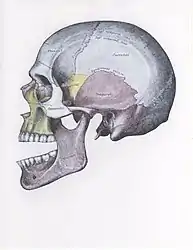

Side view of the skull with anterior dislocation of jaw.

Side view of the skull with posterior dislocation of jaw.

Side view of the skull with superior dislocation of jaw.

Front view of the skull with lateral dislocation of jaw.